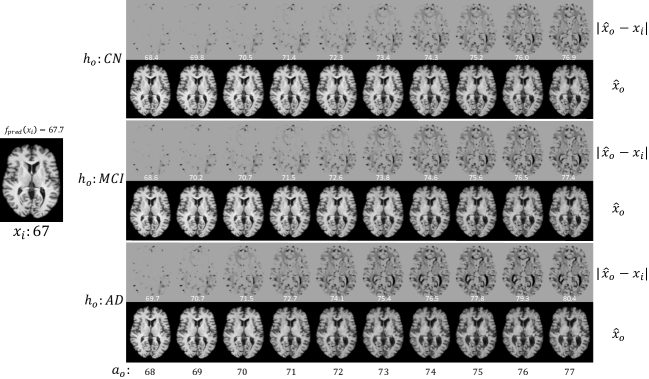

Fig. 7: Brain ageing progression for a healthy (CN) subject 𝐱isubscript𝐱𝑖\mathbf{x}_{i} (at age 67) from ADNI dataset. We synthesise the aged images 𝐱^osubscript^𝐱𝑜\hat{\mathbf{x}}_{o} at different target ages aosubscript𝑎𝑜a_{o} on different health states hosubscript𝑜h_{o}: CN, MCI and AD, respectively. We also visualise the difference between 𝐱isubscript𝐱𝑖\mathbf{x}_{i} and 𝐱^osubscript^𝐱𝑜\hat{\mathbf{x}}_{o}, |𝐱^o𝐱i|subscript^𝐱𝑜subscript𝐱𝑖|\hat{\mathbf{x}}_{o}-\mathbf{x}_{i}|, and show the predicted (apparent) ages of 𝐱^osubscript^𝐱𝑜\hat{\mathbf{x}}_{o} as obtained by our pre-trained age predictor (white text overlaid on each difference image). For more details see text.

Furthermore, we show visual results of the same subject at different target health states hosubscript𝑜h_{o}, in Fig. 7. We observe that for all hosubscript𝑜h_{o}, the brain changes gradually as age (aosubscript𝑎𝑜a_{o}) increases. However, the ageing rate varies based on health state (hosubscript𝑜h_{o}). Specifically, when hosubscript𝑜h_{o} is CN, ageing is slower than that of MCI and AD, as one would expect; when hosubscript𝑜h_{o} is AD, ageing changes accelerate. We also report the estimated ages of these synthetic images as predicted by fpredsubscript𝑓𝑝𝑟𝑒𝑑f_{pred}. While these results show one instance, we synthesised aged images of different health status from 49 ADNI test set CN subjects, with target ages 10 years older than the original age. We then used fpredsubscript𝑓𝑝𝑟𝑒𝑑f_{pred} to estimate the age of these synthetic images. We find that on average, synthetic AD images are 4.9±2.3plus-or-minus4.92.34.9\pm 2.3 years older than the target age, whereas synthetic MCI and CN images are 1.8±2.0plus-or-minus1.82.01.8\pm 2.0 and 1.5±2.1plus-or-minus1.52.11.5\pm 2.1 years older than the target age, respectively. These observations are consistent with prior findings that AD accelerates brain ageing [45]. We also observe that the gray/white matter contrast decreases as age increases, which is consistent with existing findings [63, 16].